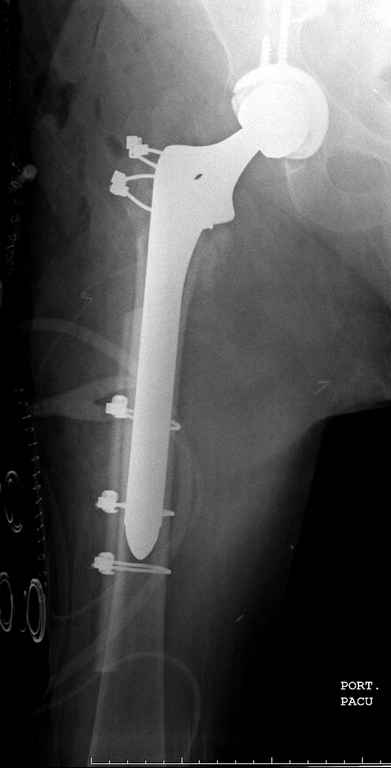

Вашему вниманию представляется похожий случай, пациентке 70, осложнился в течение одного месяца после операции. Ревизия с заменой сустава, кабельная фиксация на трохантер. При установке в дистальном диафизе обнаружен тонкий кортикальный слой и сделана профилактика от возможного перелома аллографтом.